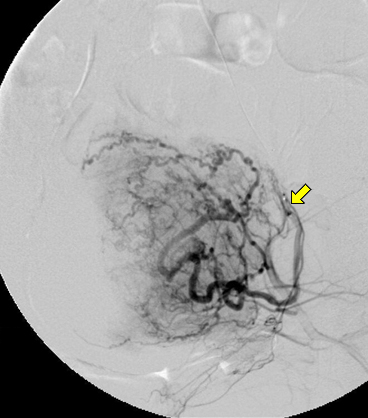

자궁근종 색전술 투시 영상: 시술 중 시행한 좌측 자궁동맥(화살표) 조영술 사진